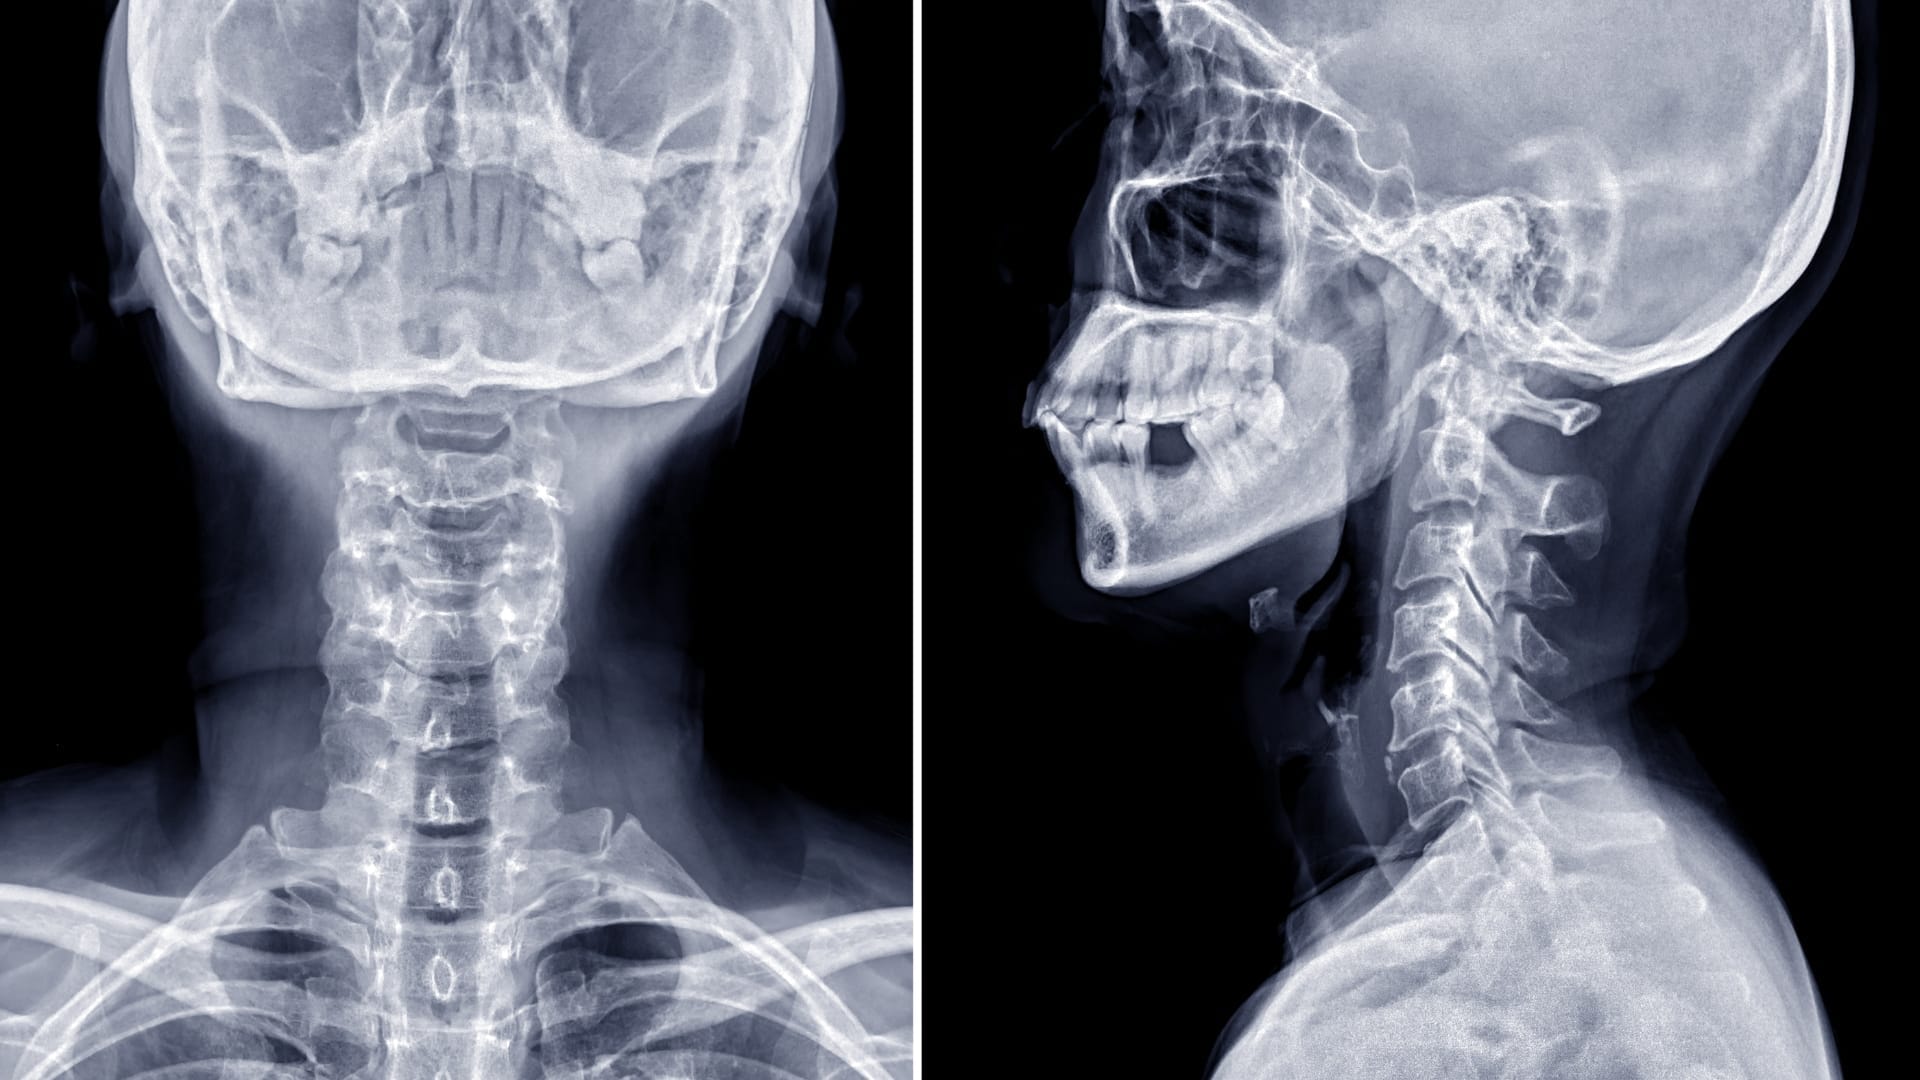

Table of Contents Definition Cervical disc herniation is the most common cause of neck pain. It occurs when the jelly-like material inside the disc acts